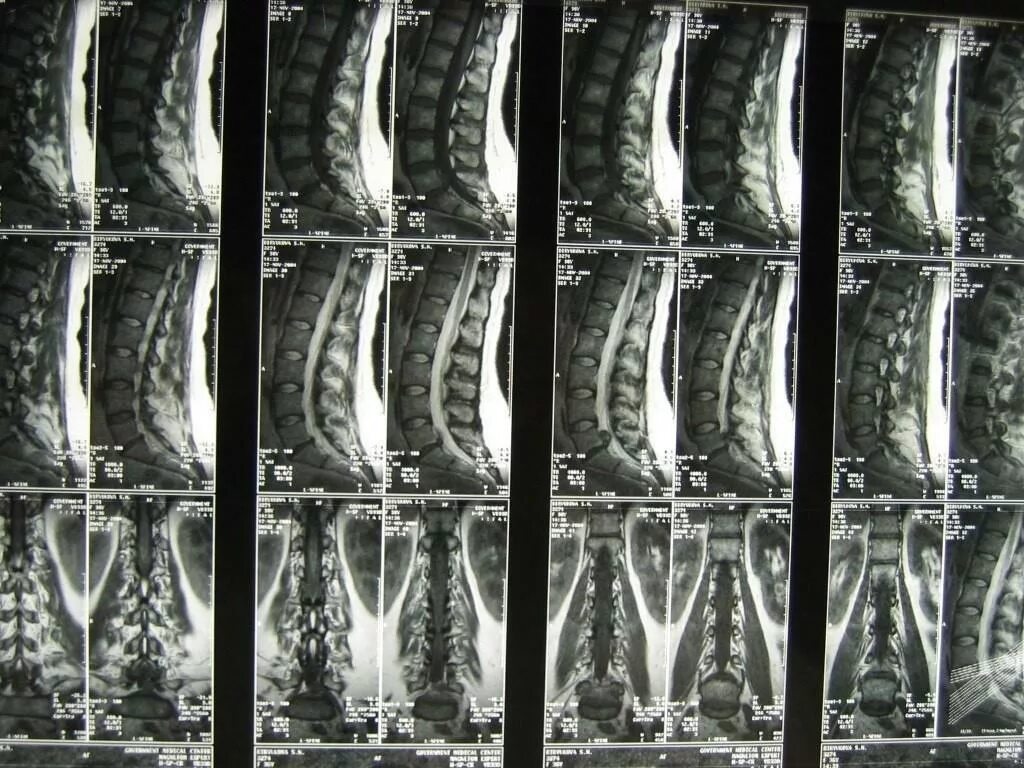

Мрт шейно поясничного отдела